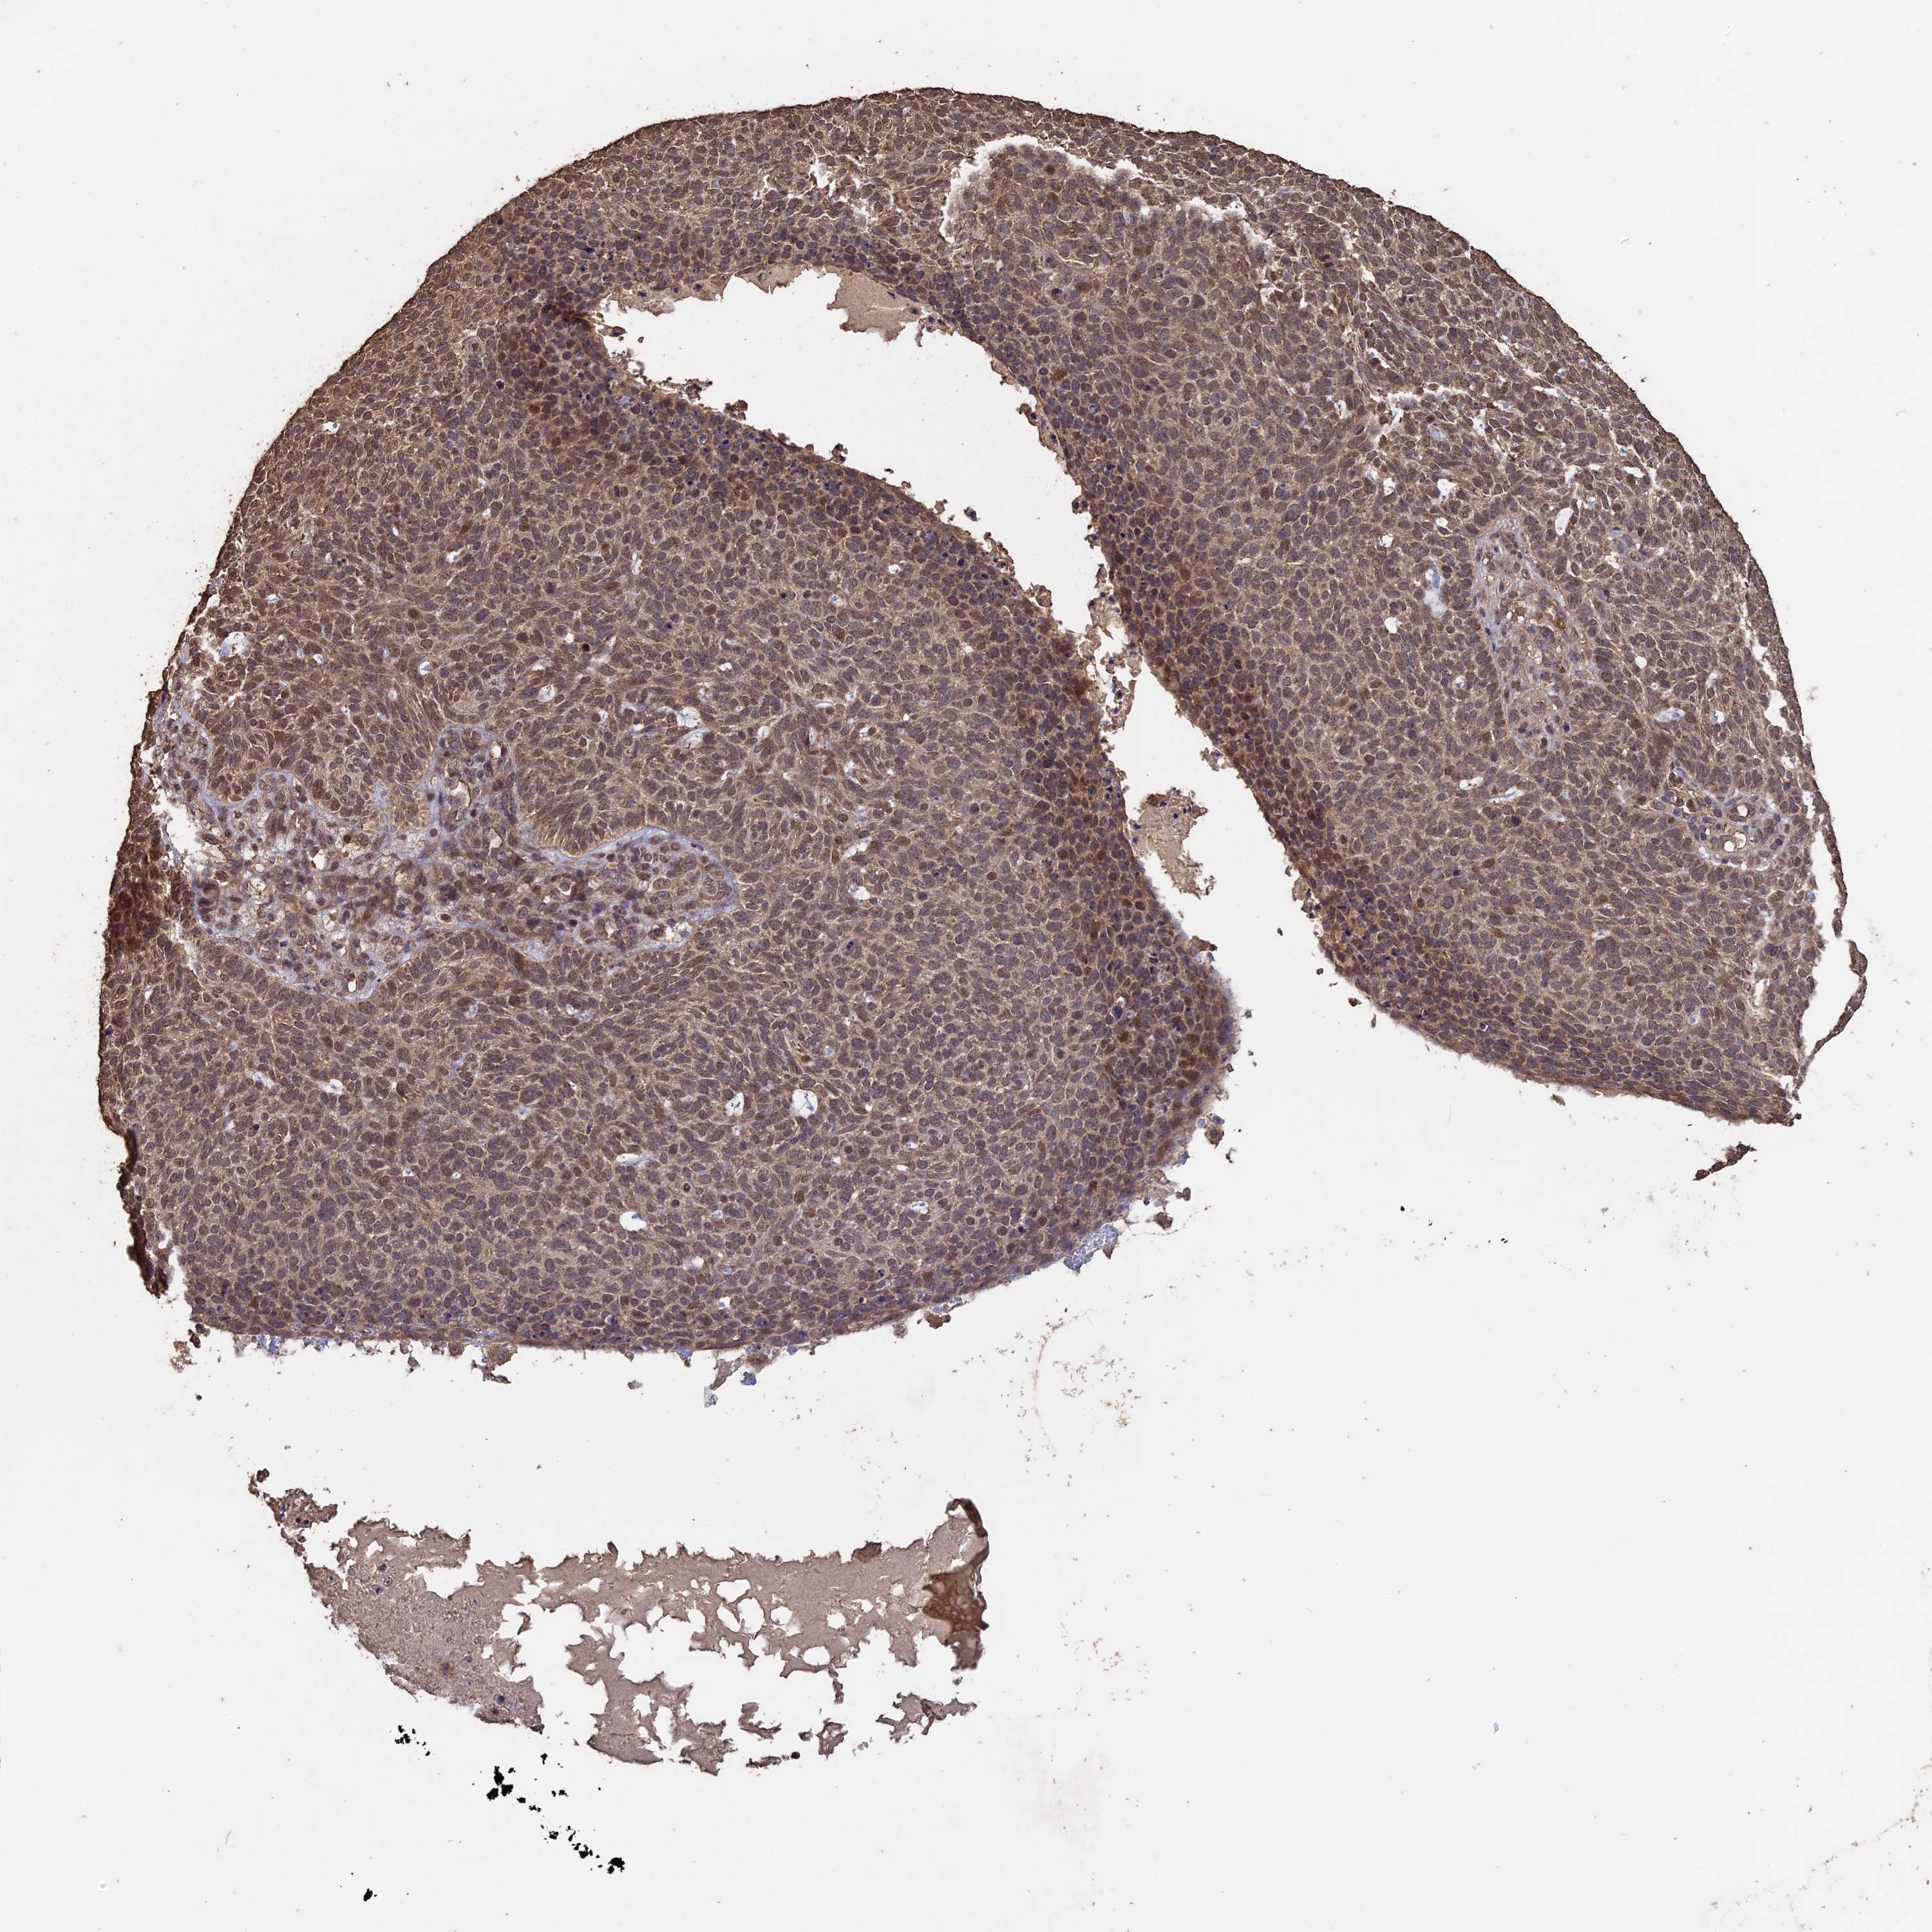

SKIN CANCER - Protein expressioni

A mouse-over function shows sample information and annotation data. Click on an image to view it in a full screen mode. Samples can be filtered based on level of antibody staining by selecting one or several of the following categories: high, medium, low and not detected. The assay and annotation is described here.

Antibody stainingi

Antibody staining in the annotated cell types in the current human tissue is reported as not detected, low, medium, or high, based on conventional immunohistochemistry profiling in selected tissues. This score is based on the combination of the staining intensity and fraction of stained cells.

Each image is clickable and will lead to virtual microscopy that enables deeper exploration of all samples and also displays staining intensity scores, fraction scores and subcellular localization as well as patient and tissue information for each sample.

Antibody HPA027295

Antibody HPA027372

Staining

High

Medium

Low

Not detected

Intensity

Strong

Moderate

Weak

Negative

Quantity

>75%

75%-25%

<25%

None

Location

Nuclear

Cytoplasmic/membranous

Cytoplasmic/membranous,nuclear

Basal cell carcinoma

Squamous cell carcinoma, NOS

Squamous cell carcinoma, metastatic, NOS